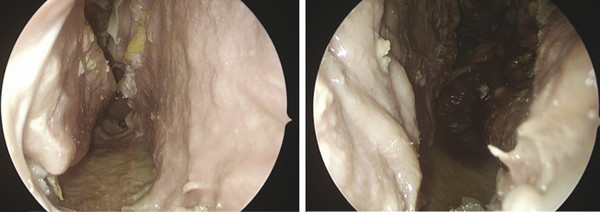

At the beginning of surgery, the nasal cavity is decongested with cottonoids impregnated with a solution of adrenalin 0.001% with lidocaine 2%. This aids with hemostasis throughout the surgery. The edges of the septal perforation are refreshed to improve their binding to the flap. 15 , 21

The flap is folded back on itself, in its most distal area, for greater thickness of new nasal septum, suturing with dissolvable stitches (Fig. 21‑2).

With an endoscopic view, the pericranial flap would be introduced into the nasal cavity through the osteotomy of the frontal sinus and rotated laterally 90 degrees to be in a sagittal plane like the nasal septum. Before that, it would be advisable to mark the extremes of the flap with stitches to facilitate insertion into the nasal (Fig. 21‑2, Fig. 21‑4).